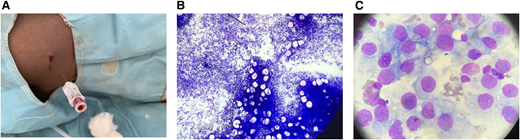

Introducing BM aspiration service

Similarly, BM aspiration was introduced to SFH in carefully selected patients to allow diagnosis and avoid the need to transfer patients to Lusaka (6 of 6 BM aspirations were successful; Table 4). Because resources are limited, we used spinal needles as described in the literature3 (Figure 5A). A clinician is currently being trained in the technique, and laboratory staff will prepare slides that can then be sent to UTH for reporting (Figure 5B-C). By the time the current morphologist leaves, procedures will be in place to ensure that BM aspirates can continue to be taken and will continue to be reported to UTH as described above.

BM aspiration procedure and aspirates. (A) BM aspiration using a spinal needle. BM smear slides showing (B) BM aspirate from a spinal needle and (C) sixth successful BM aspirate with cells indicative of suspected metastatic disease.

BM aspiration procedure and aspirates. (A) BM aspiration using a spinal needle. BM smear slides showing (B) BM aspirate from a spinal needle and (C) sixth successful BM aspirate with cells indicative of suspected metastatic disease.